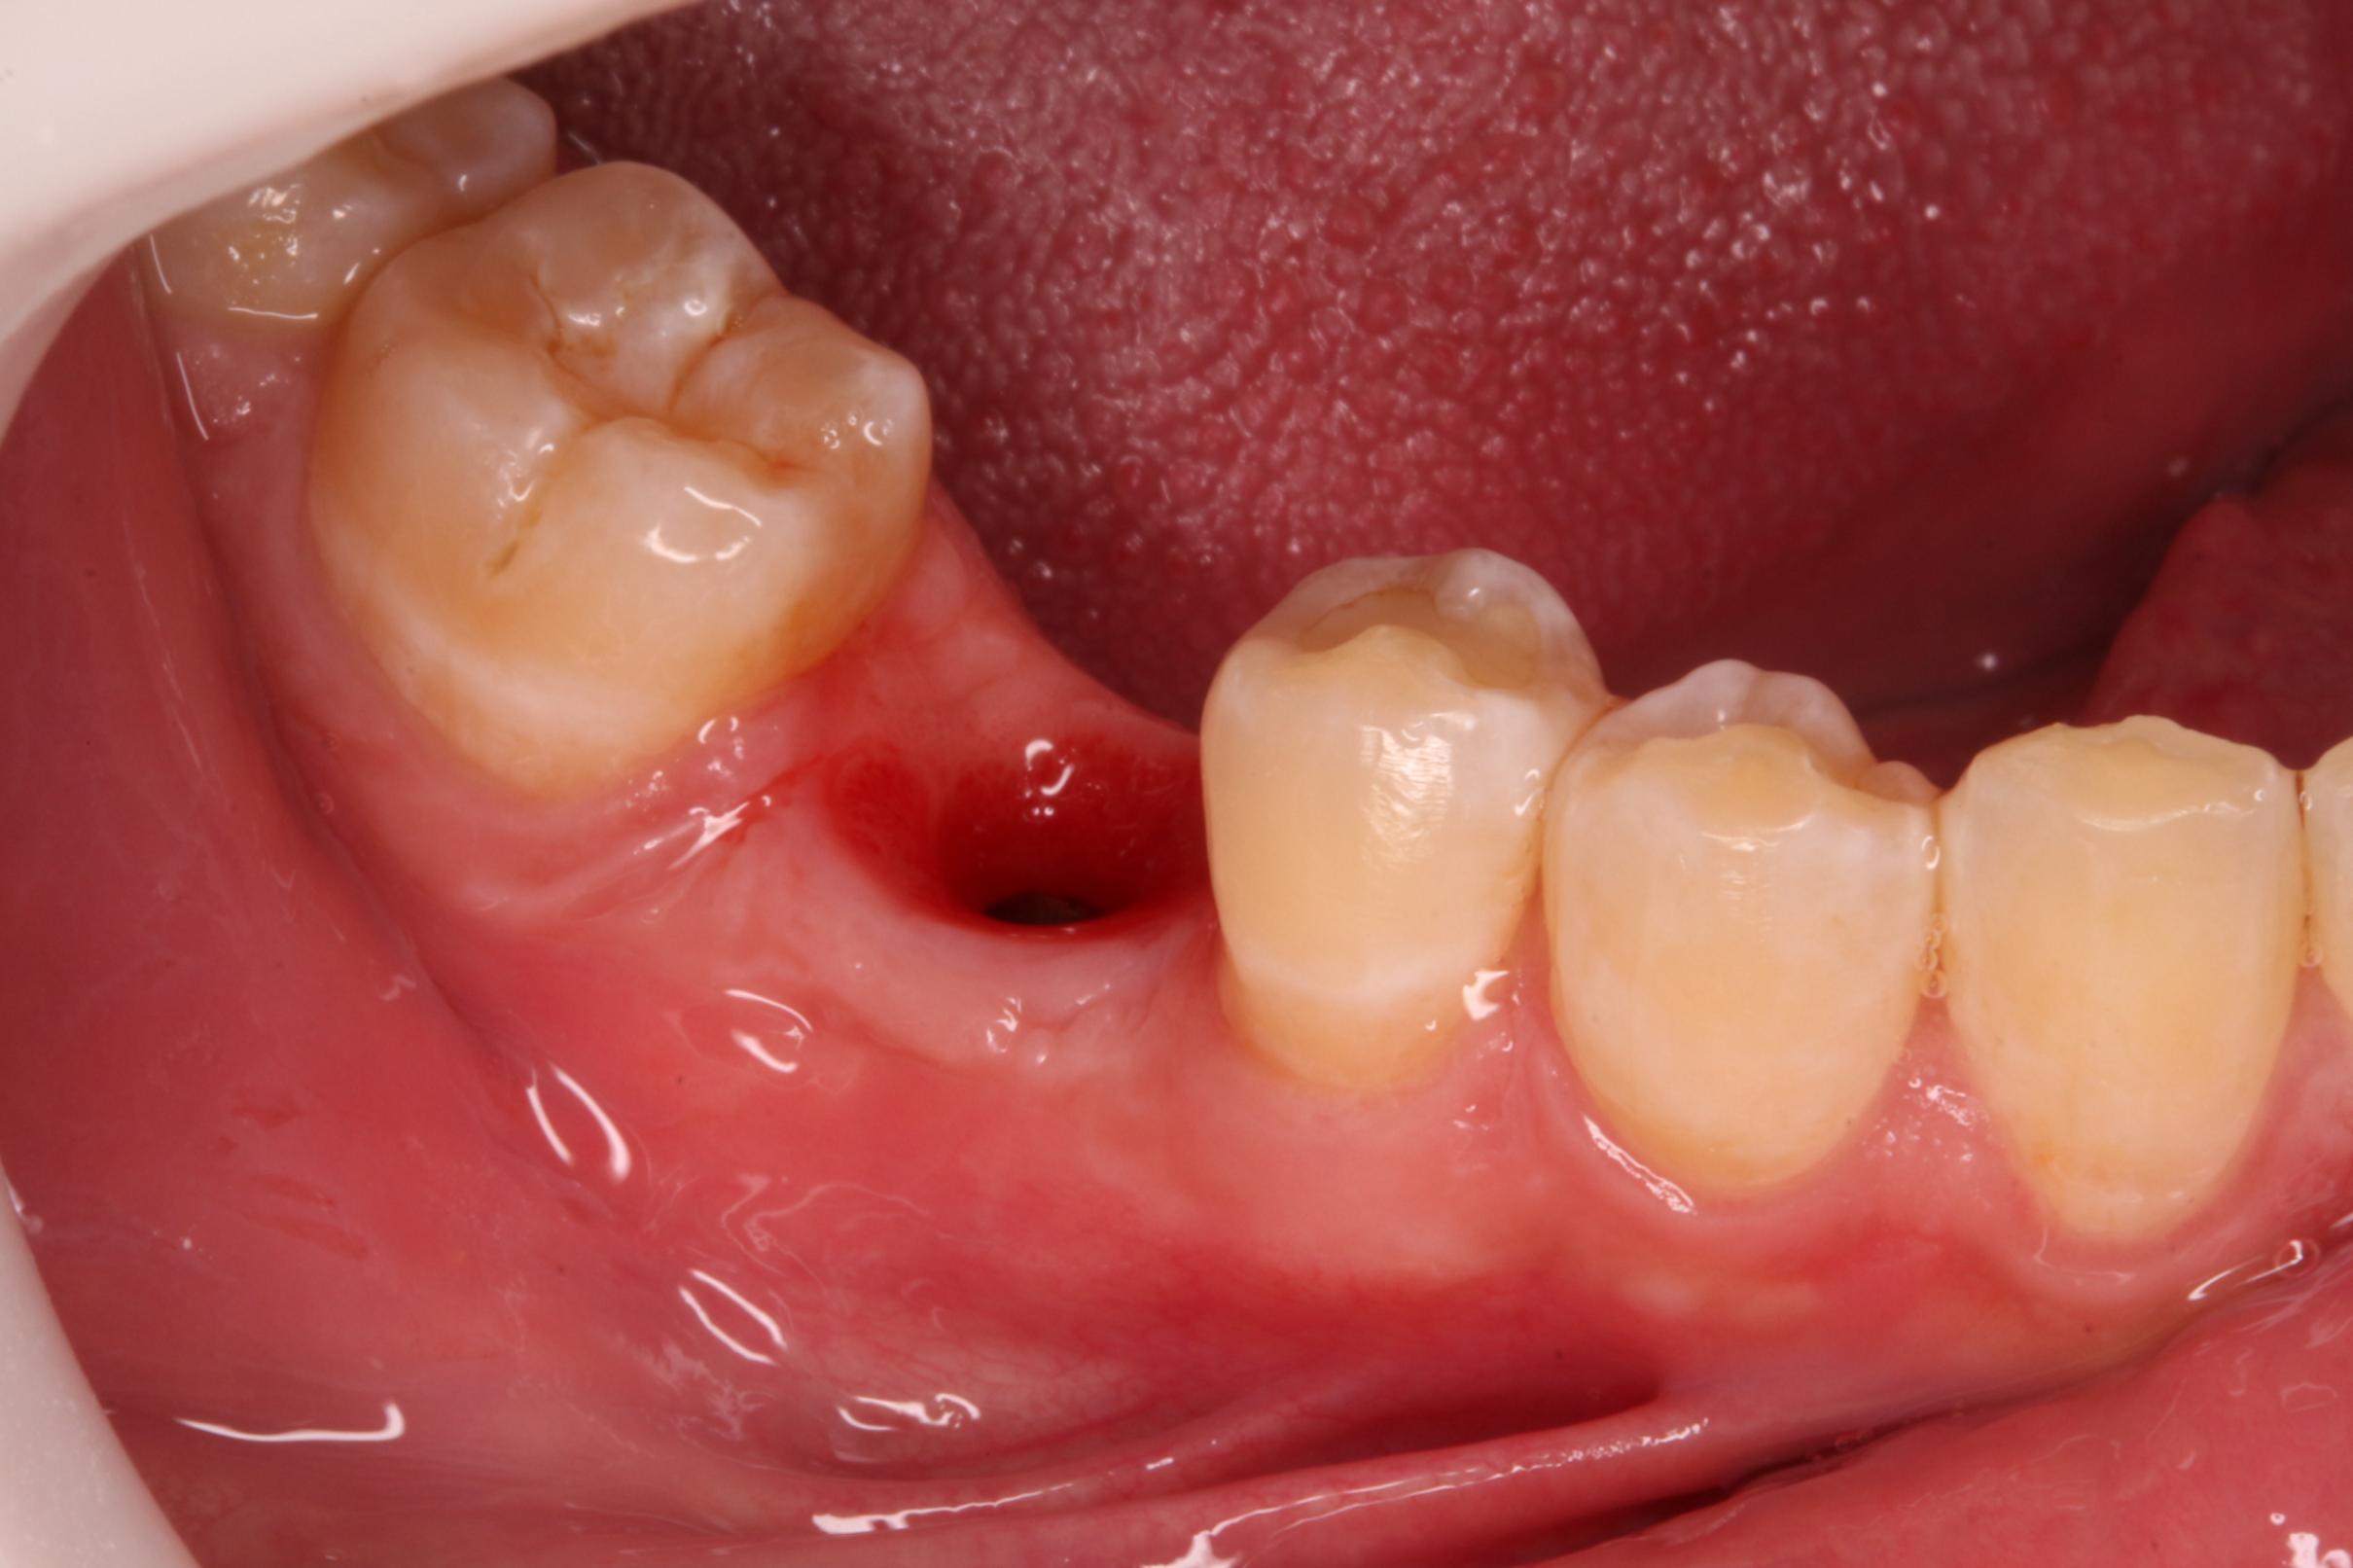

Implante y corona

Este paciente de 31 años acudió a la consulta porque había perdido una muela y deseaba rehabilitar su sonrisa. Nuestro cirujano colocó un implante dental en el espacio donde faltaba la pieza, y tras el tiempo necesario para que el implante se integrara correctamente al hueso, confeccionamos una corona en nuestro propio laboratorio. De esta manera, logramos devolverle tanto la función como la estética. El resultado fue tan natural que el paciente quedó encantado: la corona se mimetiza perfectamente con el resto de sus dientes, pasando completamente desapercibida.